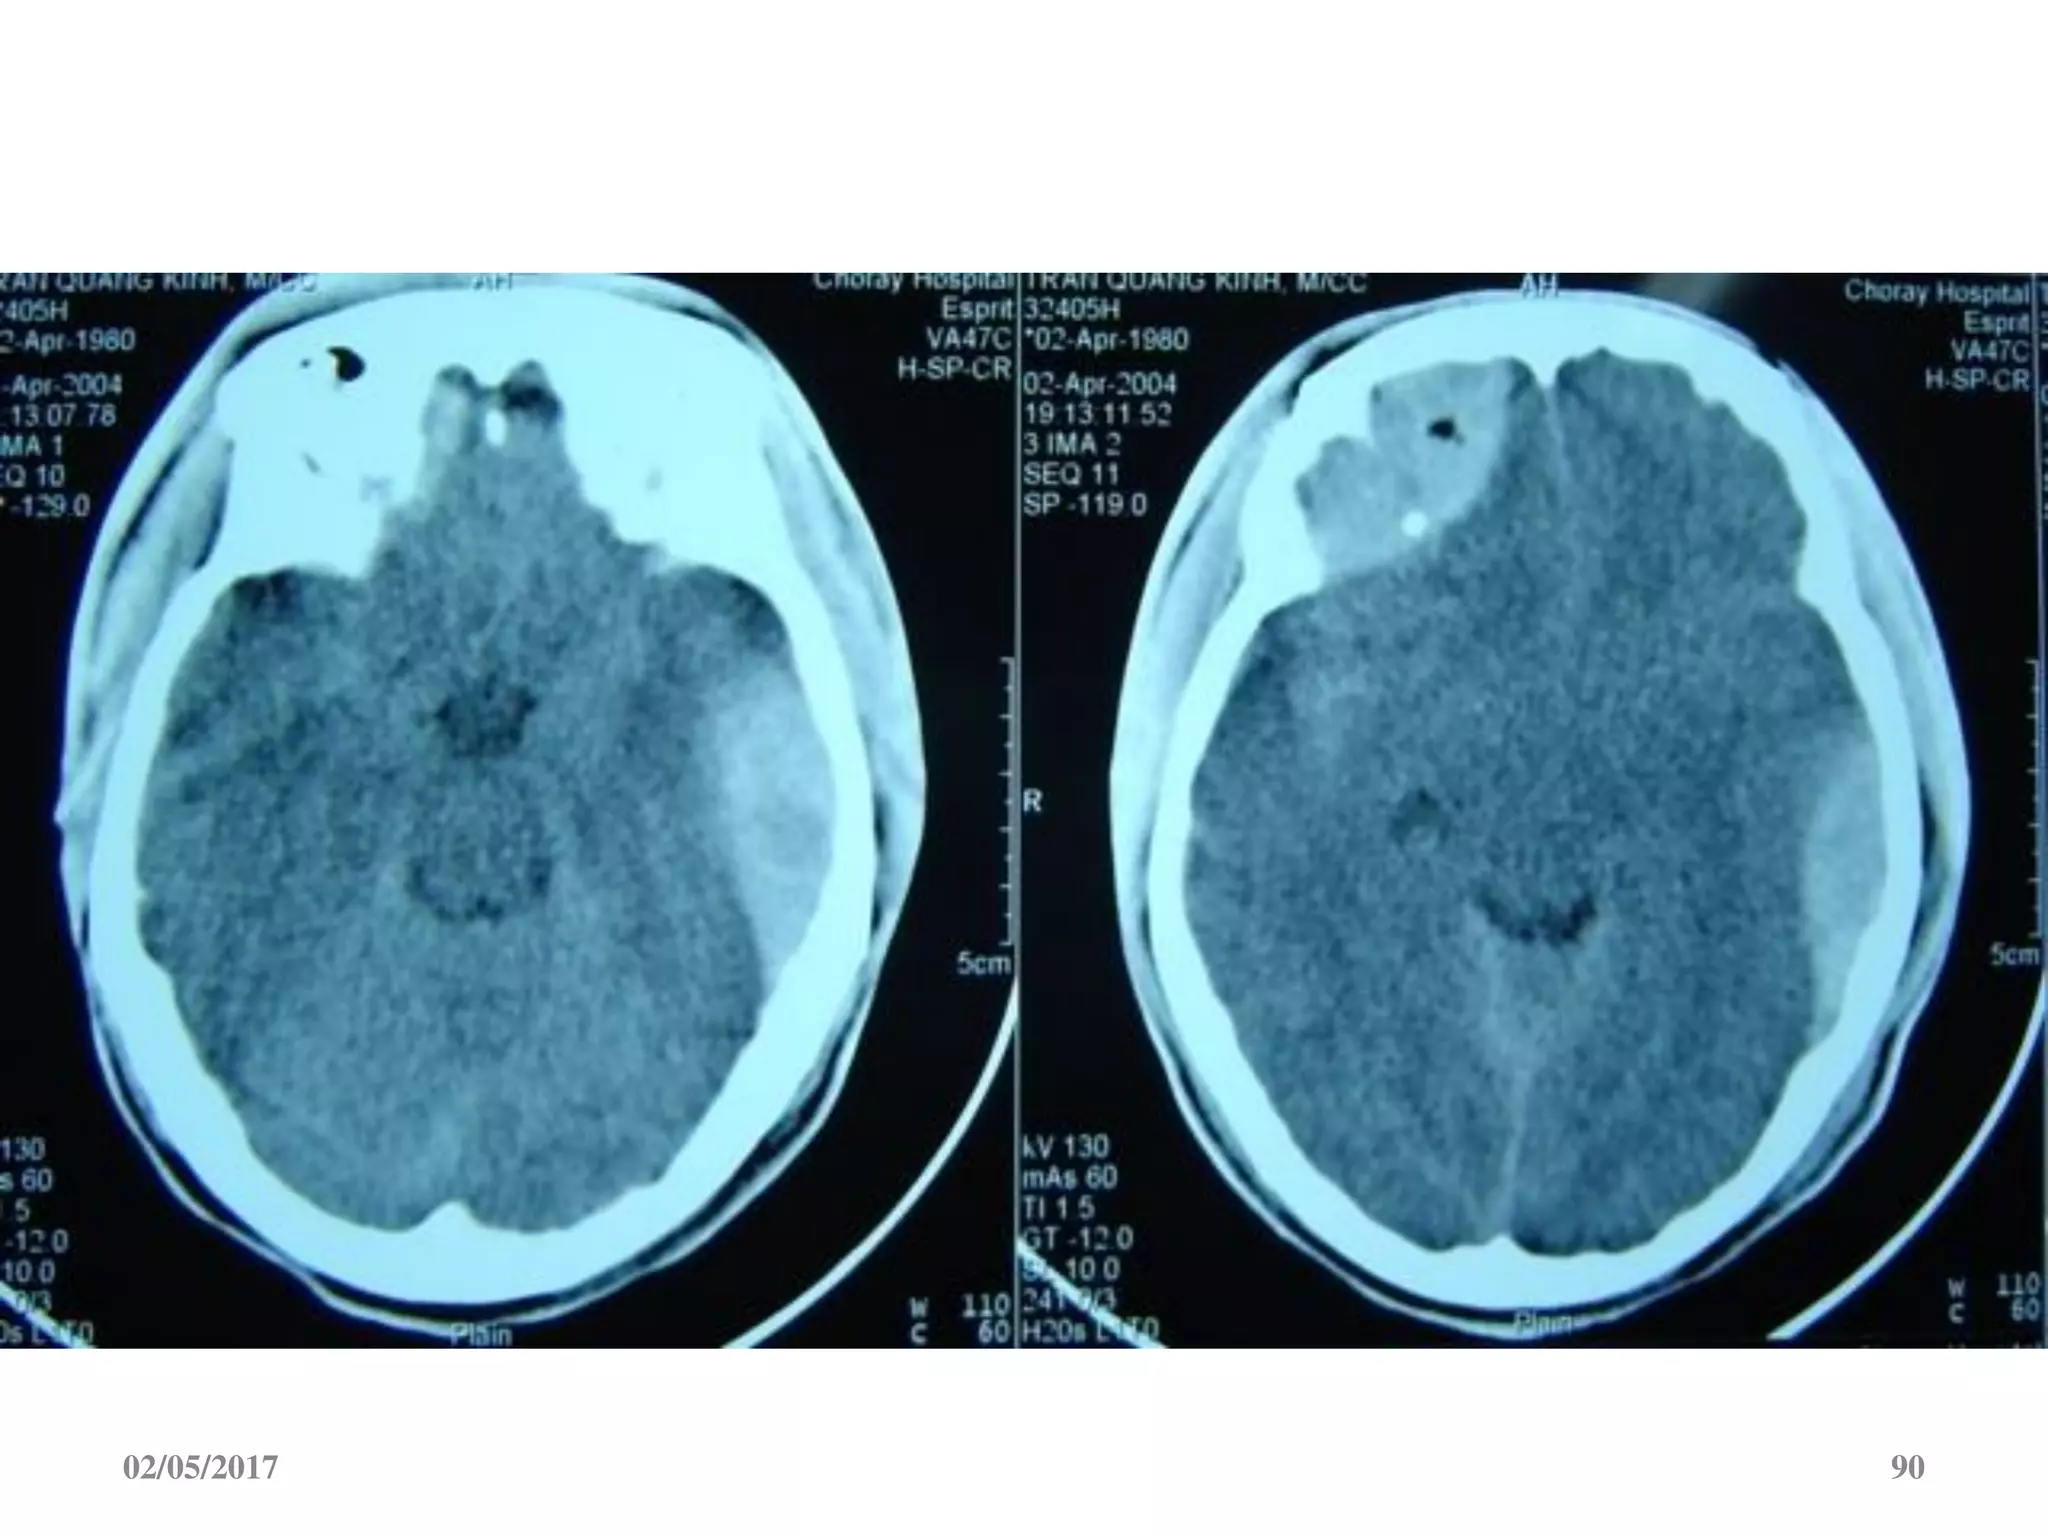

Máu tụ dưới màng cứng cấp

 Ngoài trục, hình liềm,

tăng đậm độ

 Vượt qua được các

khớp sọ

 Thường kèm dập não